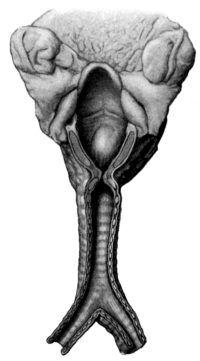

| 186. | Anatomical Preparation of the Middle Ear | 335 |